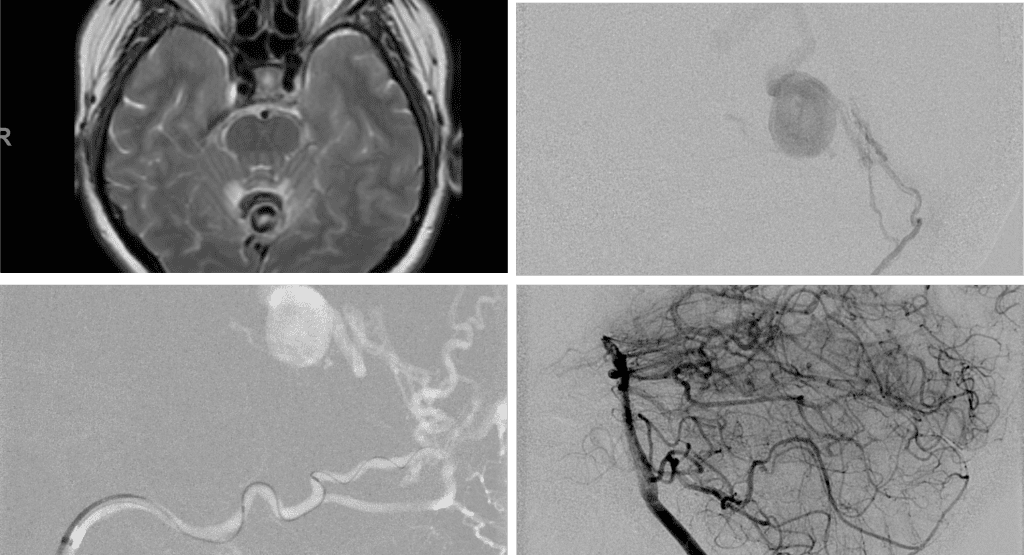

Figure 3. Right ECA AP and Lateral angiograms Pre (A and B) and Post NBCA embolization (C and D) Demonstrate near complete obliteration of right Occipital and Middle Meningeal Artery Fistulas

Figure 4. Left ECA AP and Lateral angiograms Pre (A and B) and Post NBCA embolization (C and D) Demonstrate near complete obliteration of Left Occipital Artery Fistulas.